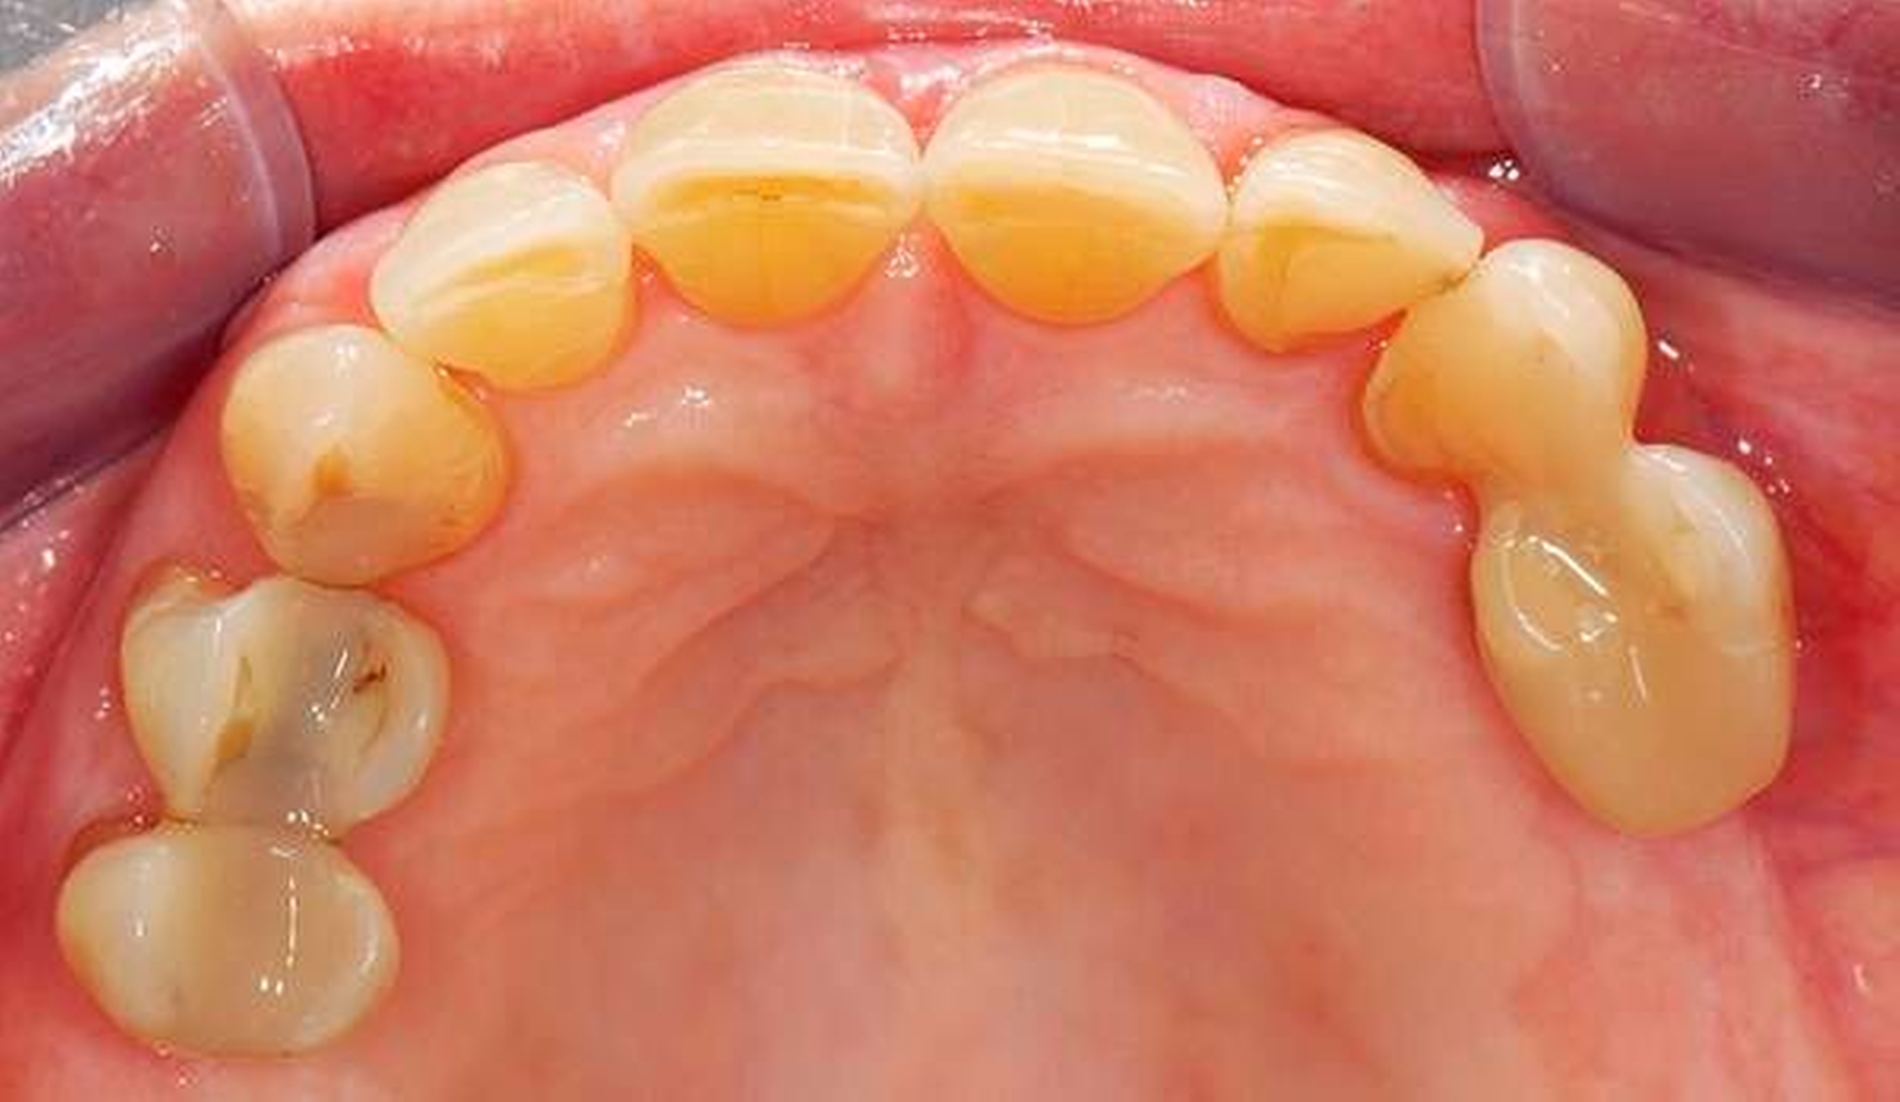

Abbildung 3: Direkte Reparatur im Seitenzahnbereich (R2-Technik)

In den Abbildungen 1 bis 3 werden Optionen für frugale Interventionen auf restaurativem Sektor aufgeführt. Es handelt sich um direkte Vollüberkronungen im Frontzahnbereich (hier: hergestellt in R1-Technik / einphasig) (Abbildung 1), direkte Teilüberkronungen im Seitenzahnbereich (hier: hergestellt in R1-Technik / einphasig) (Abbildung 2), Reparatur-Restaurationen im Seitenzahnbereich (hier: hergestellt in R2-Technik / zweiphasig) (Abbildung 3). Technische Einzelheiten zur Vorgehensweise und den Ergebnissen sind an anderer Stelle beschrieben (Literatur siehe oben).

schadensgerechte Reparaturtechniken (Abbildung 3),